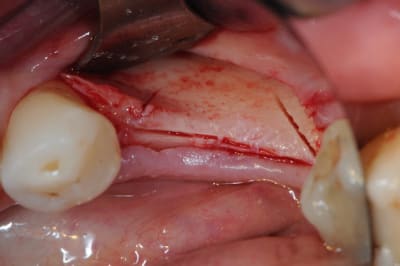

Bravo D57 pour ta chirurgie de reconstruction avec le systeme Fast.

mais j'ai quelques remarques:

1. tes vis ne sont pas positionnées comme il faut.

2. tes vis sont trop enfouies

3. tes sutures ne sont pas assez profondes. comme je te le disais à l'ADF, tu dois être à au moins 1 cm de la berge.

4. Donc, je peux te le dire d'avance: le résultat sera moyen. Je t'avais proposé de préparer ensemble le protocole chirrugical. dommmage.